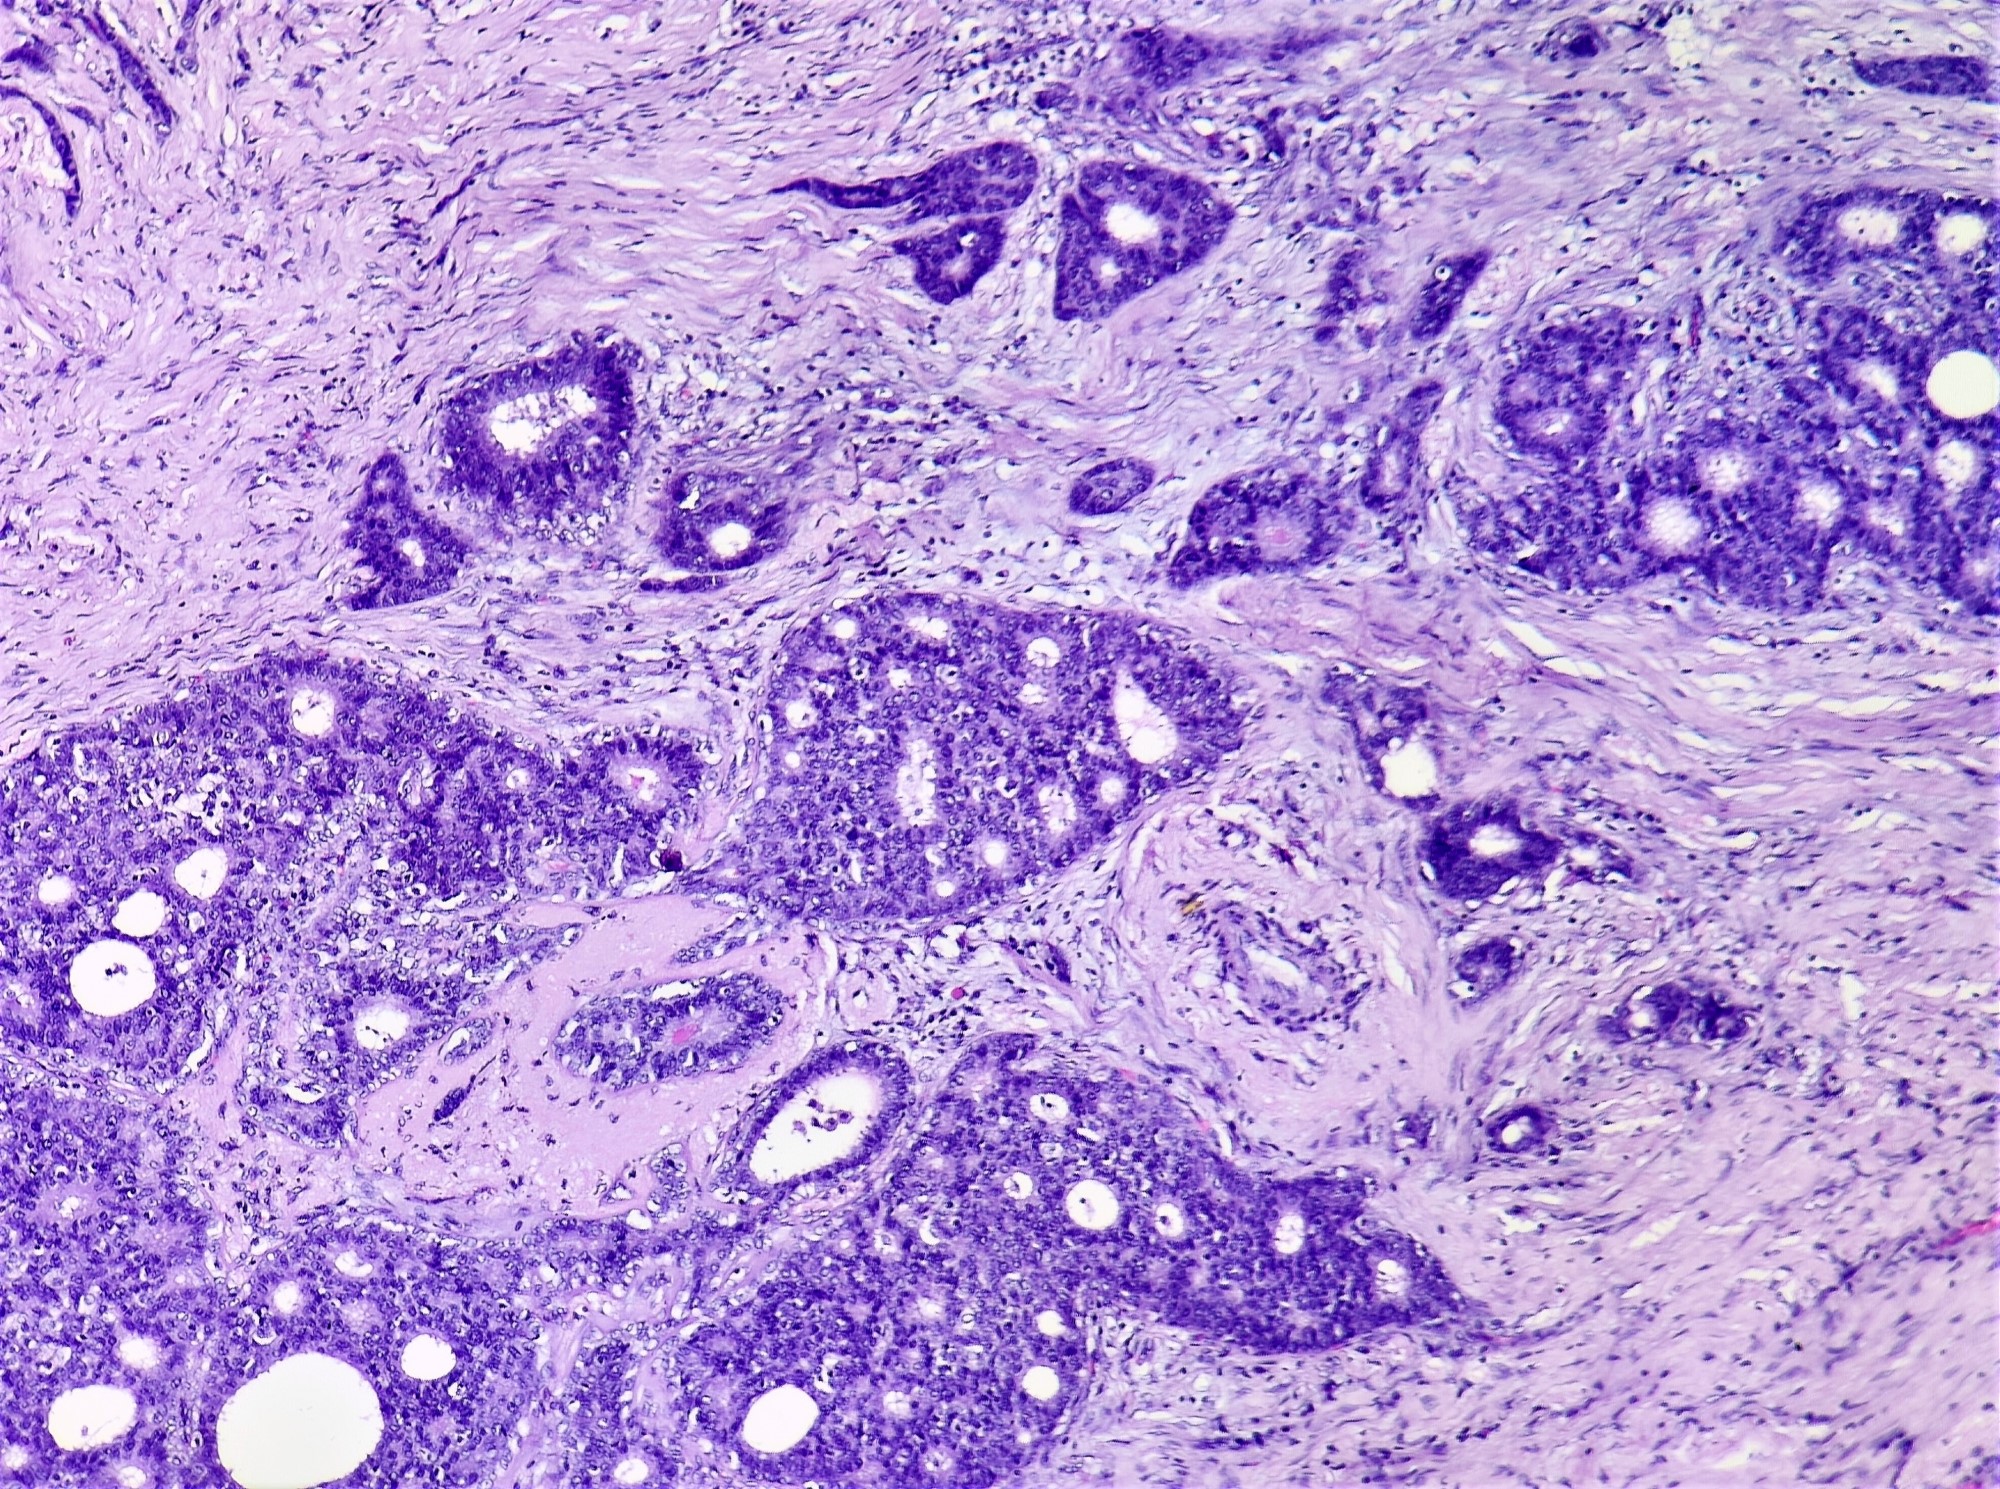

Microscopic (histologic) description

- Irregular cribriform growth pattern > 90% of cells

- Nuclear grade I pure ICC: > 90% cribriform pattern

- Mixed: 10 - 90% other morphological type, other than cribriform carcinoma

- Low grade: Nottingham grade 1 tumors

- Invasive islands or nests of malignant cells with round or angulated contours and well defined cribriform spaces formed by arches of epithelial cells; this gives a sieve-like appearance

- Tumor cells: small, mild / moderate pleomorphism, no nuclear atypia

- No / sparse mitotic activity

- Desmoplastic stroma

- Mucin positive secretion, microcalcifications in lumen

- Osteoclastic giant cells may be seen

- Myoepithelial cells absent

- Associated with cribriform ductal carcinoma in situ (DCIS)

Microscopic (histologic) images

Contributed by Sunitha Shankaralingappa, M.B.B.S, M.D., D.M.